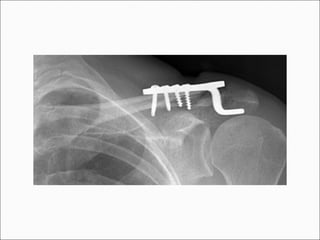

 Clavicular Hook Plate

• The Hook Plate (Synthes USA, Paoli, PA)

was specifically designed to avoid this

problem of redisplacement.

Hook Plate - Results

 Recent series of distal clavicle fractuers treated with

the Hook Plate document high union rates of 88% -

100%. Complications are rare but potentially

significant, including new fracture about the implant,

rotator cuff tear, and frequent subacromial

impingement.